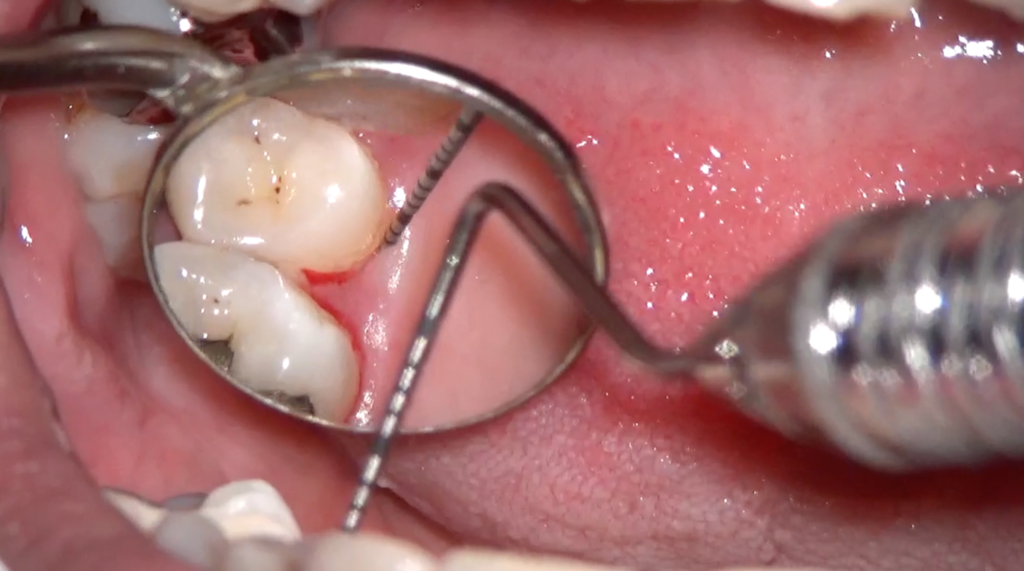

顕微鏡(マイクロスコープ)で歯石を取るメリット

① 圧倒的な視認性(最大20倍前後)

歯科用顕微鏡を使うと、

歯石の位置

大きさ

形状

歯根の凹凸

を直接目で確認しながら処置できます。

これは「感覚」ではなく「視覚」に基づい…